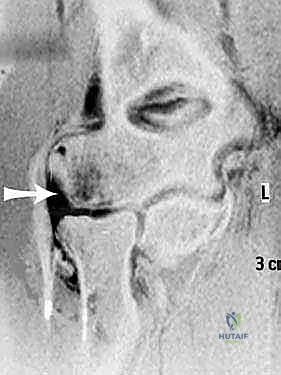

التصوير الطبي المتقدم

- الأشعة السينية (X-rays): لاستبعاد وجود كسور قديمة، تكلسات في الأربطة، أو تشوهات عظمية مثل الكوع الأفحج. في بعض الأحيان، قد تظهر الأشعة تكلساً صغيراً عند منشأ الرباط (علامة أوزبورن-كوتريل).

- التصوير بالرنين المغناطيسي (MRI): هو المعيار الذهبي لتصوير الأنسجة الرخوة. يستخدم الدكتور هطيف أجهزة رنين مغناطيسي عالية الدقة لتقييم مدى تمزق مركب الرباط الجانبي الوحشي (LUCL)، بالإضافة إلى فحص الغضاريف والأوتار المحيطة. في بعض الحالات المعقدة، قد يتم حقن صبغة داخل المفصل (MR Arthrogram) لزيادة دقة التشخيص.

- التصوير التألقي الحي (Fluoroscopy): فحص بالأشعة السينية الحية أثناء الحركة، يتم إجراؤه أحياناً تحت التخدير لتأكيد عدم الاستقرار قبل بدء الجراحة مباشرة.